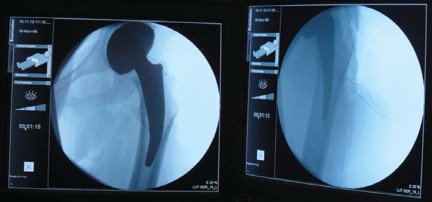

التصوير الإشعاعي

تُعد الأشعة السينية (X-rays) الأداة التشخيصية الأساسية لتصوير مفصل الفخذ. يُطلب عادة:

* صورة شعاعية أمامية خلفية (AP) للحوض مع كلا مفصلي الفخذ: هذه الصورة تسمح بتقييم شامل لكلا المفصلين، وتحديد مركز رأس الفخذ، وطول الساق، والإزاحة (offset)، ومستوى قطع عنق الفخذ المحتمل، وحجم الجذع.

* صورة شعاعية جانبية للمفصل المصاب مع تكبير 15%: لتوفير رؤية إضافية لهيكل المفصل وتخطيط الزرع.

التخطيط قبل الجراحة

يُعد التخطيط الدقيق قبل الجراحة أمرًا بالغ الأهمية لنجاح جراحة METHA قصير الجذع. يتضمن ذلك استخدام قوالب خاصة على الأشعة السينية لـ:

* تحديد حجم الزرعة: اختيار الحجم المناسب للجذع والمكون الحُقي.

* تخطيط قطع عنق الفخذ: يجب أن يكون القطع بزاوية 50 درجة بالنسبة للمحور الطولي لعظم الفخذ، مع الحفاظ على 5-10 ملم من القشرة الجانبية لعنق الفخذ.

* استعادة ميكانيكا المفصل: ضمان استعادة مركز رأس الفخذ، وطول الساق، والإزاحة إلى الوضع الفسيولوجي الطبيعي.

* تحديد زاوية عنق الفخذ: تُقاس زاوية عنق الفخذ في الجانب غير المصاب إن أمكن، لمساعدة الجراح في اختيار محول العنق المناسب أثناء الجراحة.

تساعد هذه الخطوات الدقيقة في ضمان اختيار الزرعة المناسبة وتحديد موضعها الأمثل، مما يقلل من مخاطر المضاعفات ويحسن النتائج الوظيفية للمريض. يتمتع الأستاذ الدكتور محمد هطيف في صنعاء بخبرة واسعة في التخطيط الدقيق وتنفيذ هذه الجراحات المعقدة، مستخدمًا أحدث التقنيات لضمان أفضل النتائج لمرضاه.